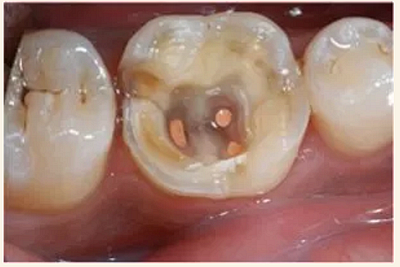

根管治療術(shù)又稱牙髓治療,是牙醫(yī)學(xué)中治療牙髓壞死和牙根感染的一種手術(shù)。該手術(shù)保留了牙齒,先是揭開髓室,頂敞開通路,用拔髓針拔除感染的牙髓。在用擴(kuò)挫針擴(kuò)凈根管壁,之后在根管內(nèi)封消炎藥,最后再用牙膠尖充填,手術(shù)繁瑣,一般要2-4次就診才能完成。隨著技術(shù)和材料的進(jìn)步,活髓牙一次性根管治療術(shù),也在臨床應(yīng)用。

1.開髓:即將患牙打開,暴露髓腔。